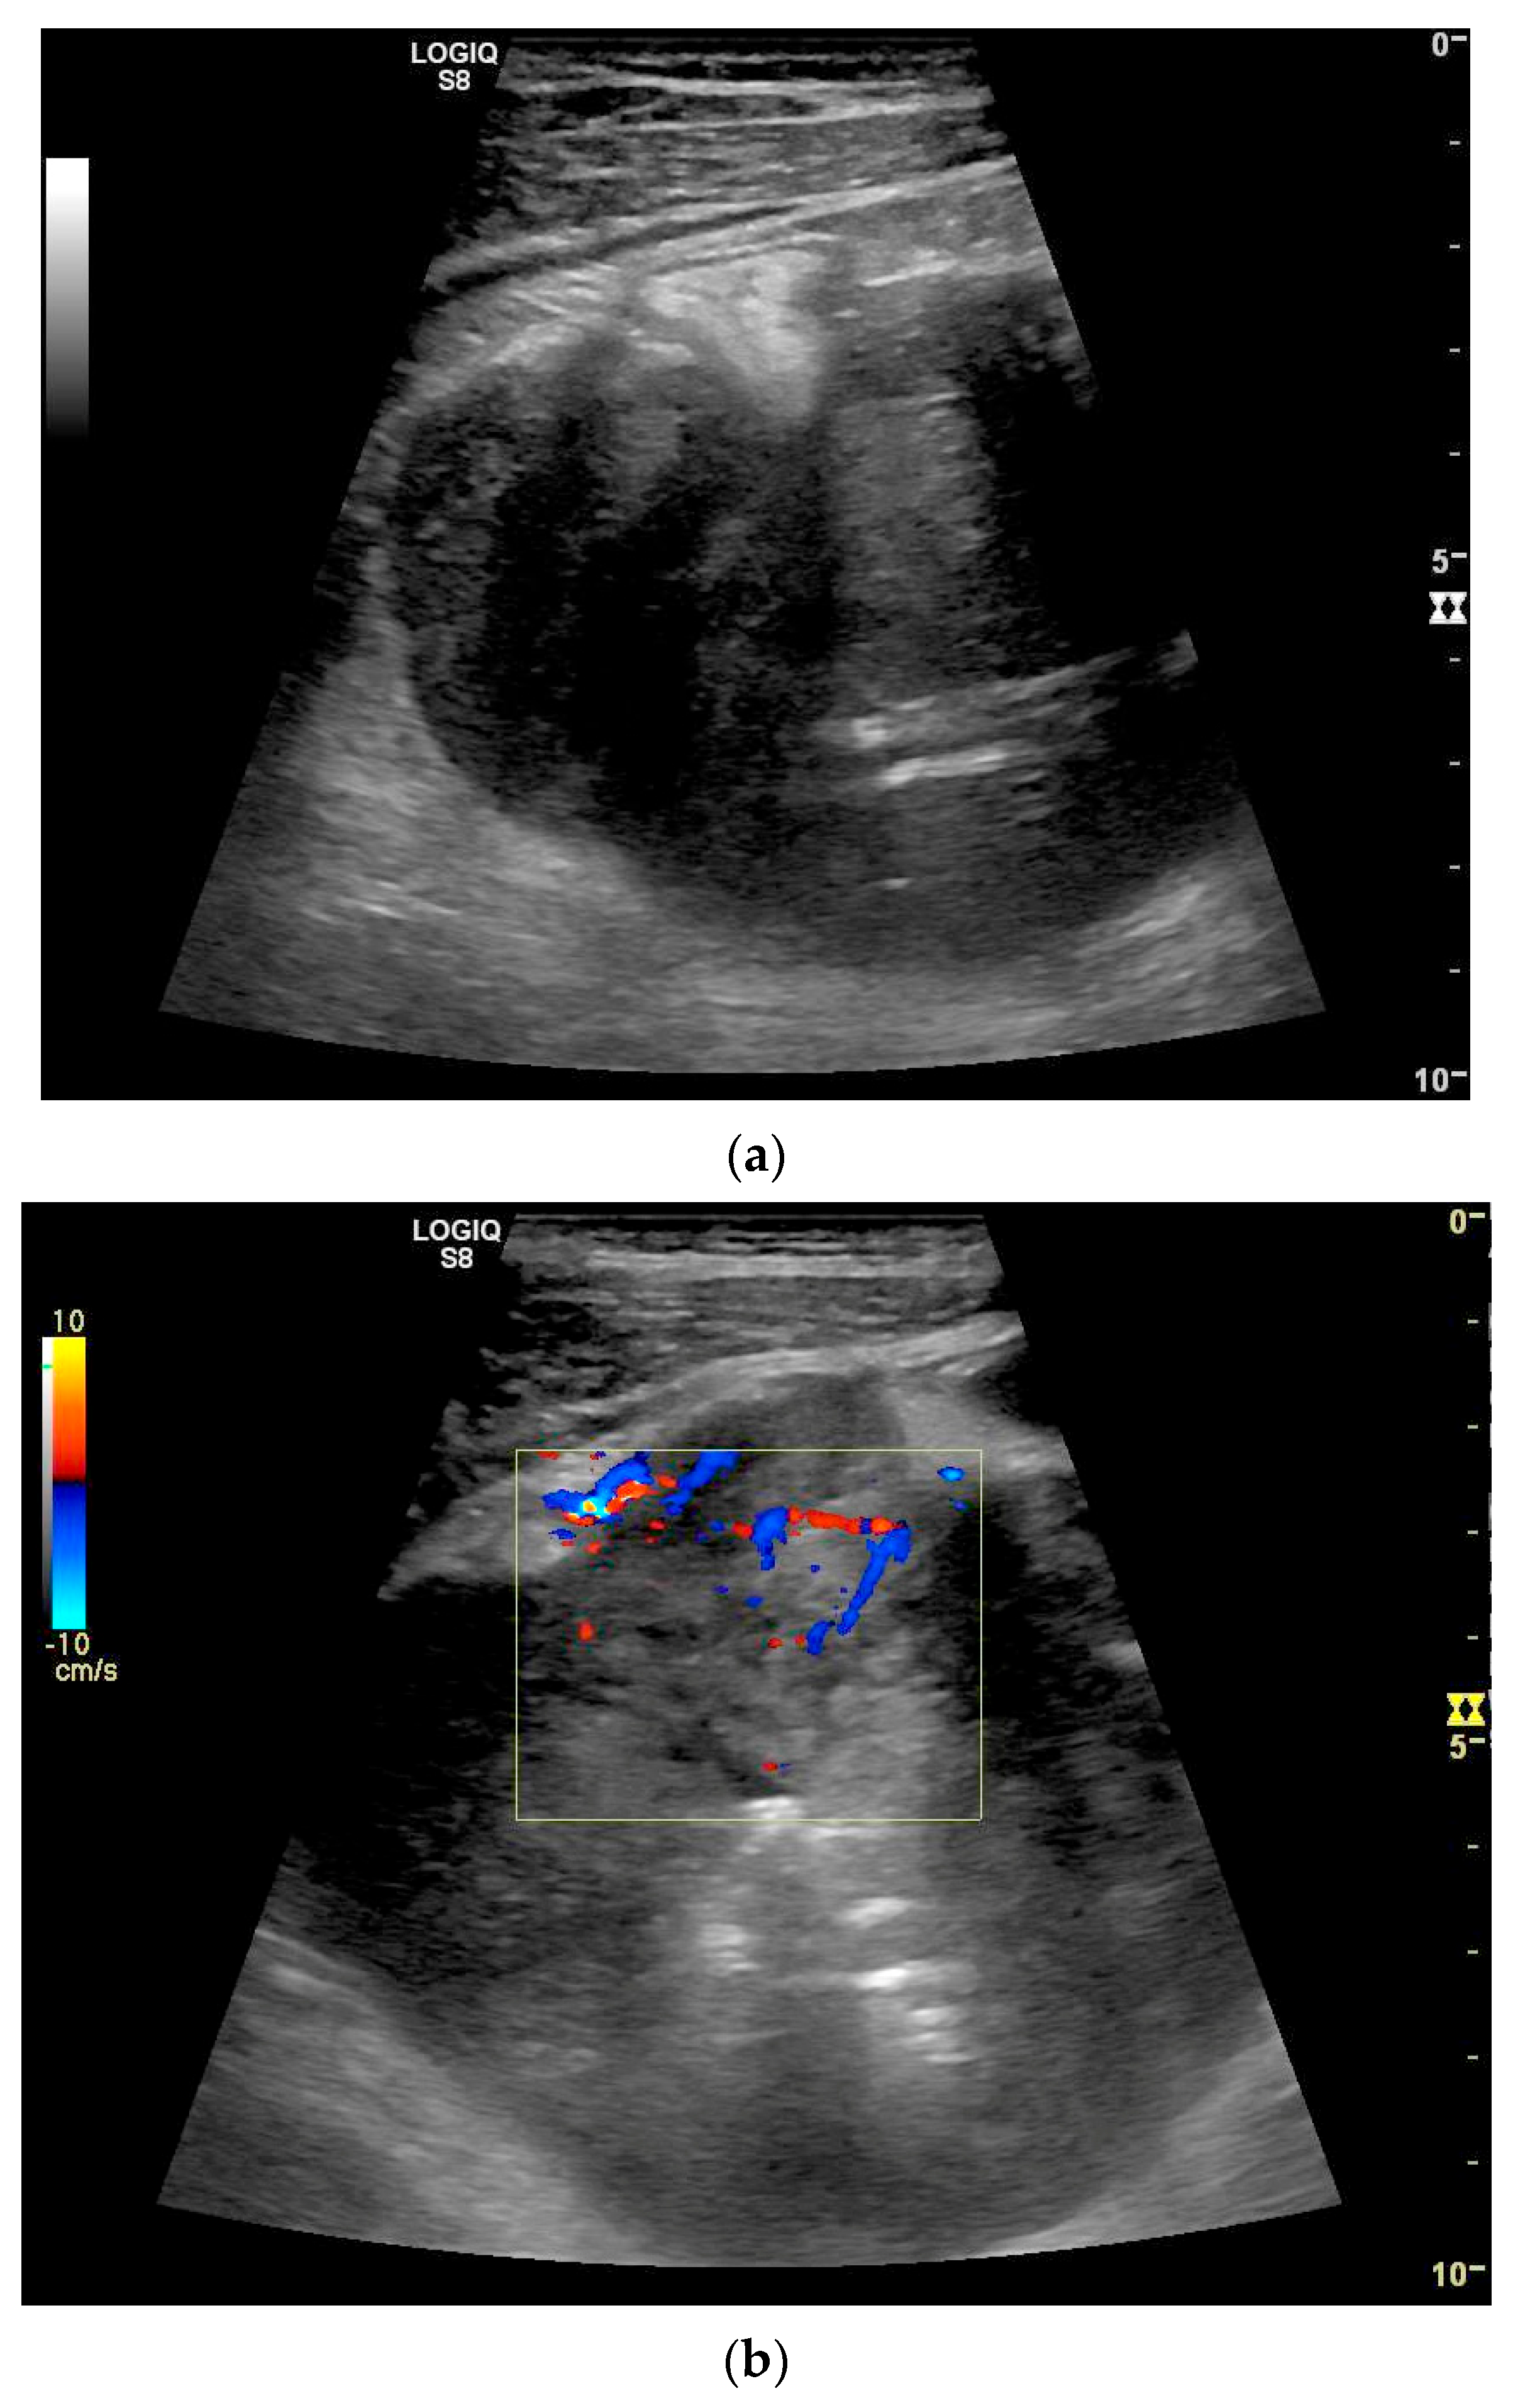

| Lymphoma | Very pronounced wall thickening with marked hypoechogenicity. Large regional and distant lymph nodes. Look for splenic infiltration. Tumor vessels on CDI and hyperenhancement on CEUS. Heterogeneous hyperechogenicity of the mesentery with walling of the mesenteric vessels. Multiple localizations are possible. |

- Cui, N.Y.; Gong, X.T.; Tian, Y.T.; Wang, Y.; Zhang, R.; Liu, M.J.; Han, J.; Wang, B.; Yang, D. Contrast-enhanced ultrasound imaging for intestinal lymphoma. World J. Gastroenterol. 2021, 27, 5438–5447. [Google Scholar] [CrossRef]